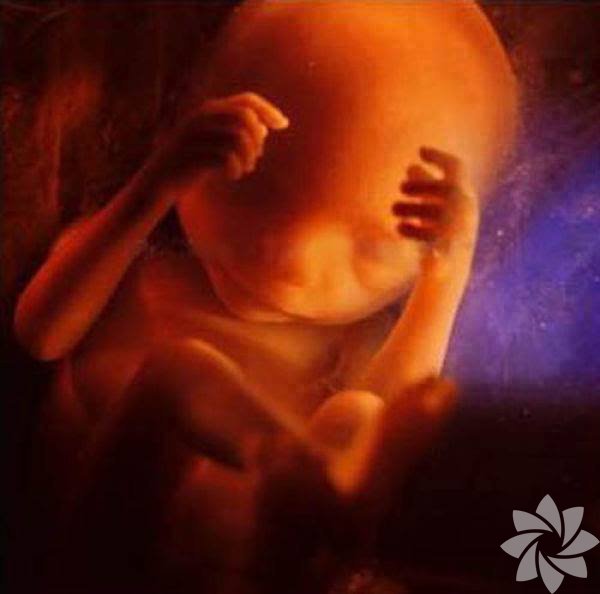

16. hafta

16. hafta, bebeğin elleri-ayakları belirginleşiyor.

Kan damarları incecik derinin altında gözüküyor ve bacaklar hareket ediyor!